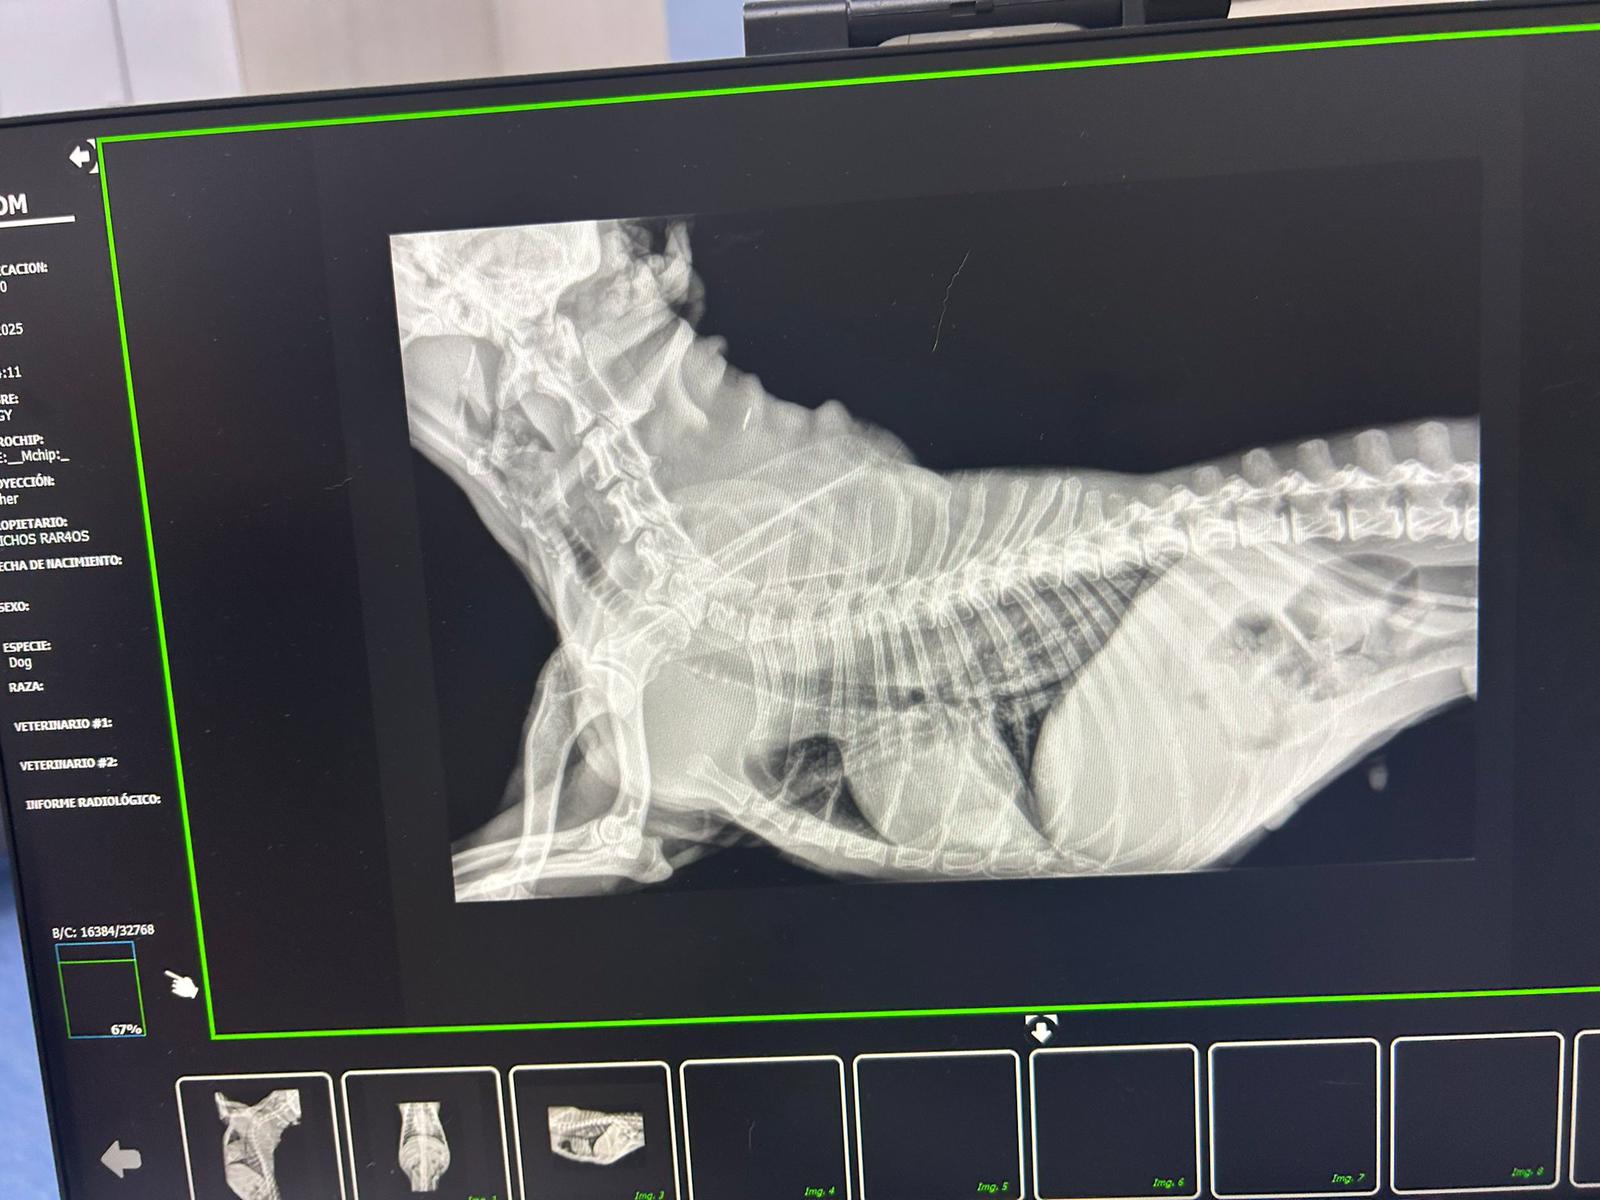

PEGGY: Debido a que su situación no mejoraba, hoy ha estado en el veterinario y, tras realizarle varias pruebas, sospechan que pueda tener un megaesófago. Para poder asegurar el diagnóstico, le harán el lunes una endoscopia, ¡así que toda nuestra energía positiva para esta chiquitina para que todo salga bien el lunes!